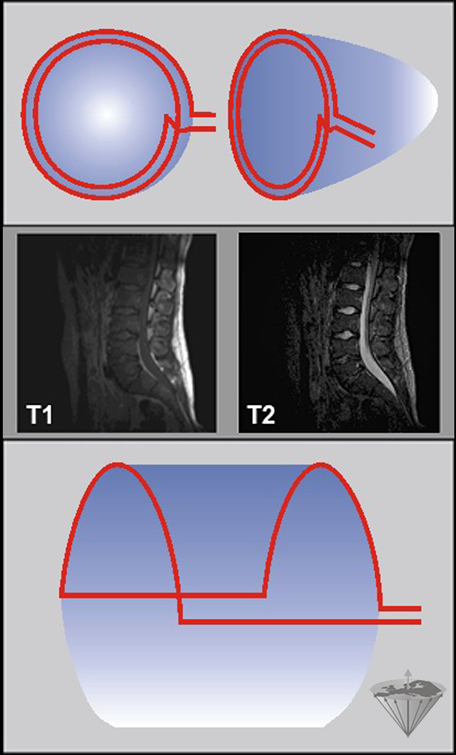

Figure 03-13:

Surface coils.

Top: Diagram of a simple surface coil. Since the in­tensity of the RF field varies with depth, the pulse an­gle will also vary with depth unless special ('adia­batic') pul­ses are used. Similarly, the de­tec­tion sen­si­t­i­vi­ty will also decrease with increasing depth.

Center: T1- and T2-weighted images of surface coil acquisitions of the lumbar spine. Spinal cord and spine are well de­pic­ted, but there is hardly any signal from the anterior parts of the pelvis.

Bottom: Wrap-around or half saddle-shape surface coil.